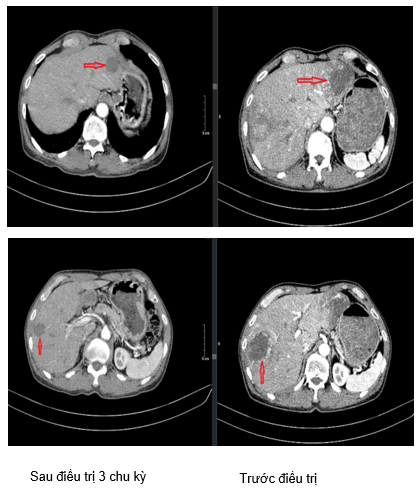

Hình 1. Hình ảnh tổn thương phổi phải phát triển lan vào trung thất: Sau 3 chu kỳ điều trị kích thước giảm xuống còn khoảng 16x29mm (hình bên trái) so với trước điều trị kích thước khoảng 62x65mm (hình bên phải).

Hình 2. Hình ảnh tổn thương nhu mô thùy dưới phổi phải sát rãnh liên thùy: Sau 3 chu kỳ điều trị kích thước giảm xuống còn 28x18mm (hình bên trái) so với trước điều trị kích thước 45x36mm (hình bên phải).